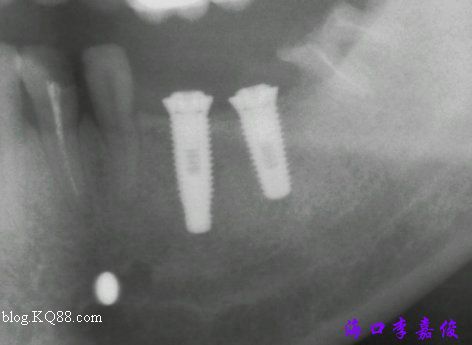

下牙術(shù)前

36種植窩成形后要植入4.8X13mm植體

37種植窩成形后植入4.8X10mm植體

術(shù)后